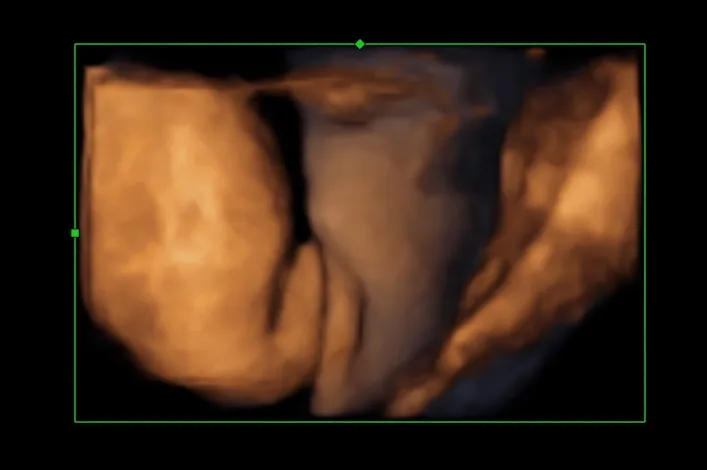

- USG 3D - daje trójwymiarowy obraz płodu, co może ułatwić identyfikację płci.

- USG 4D - pozwala na obserwację ruchów płodu w czasie rzeczywistym oraz lepszą wizualizację narządów płciowych.

| USG 4D | Obraz w czasie rzeczywistym, pozwalający na obserwację ruchów dziecka. |